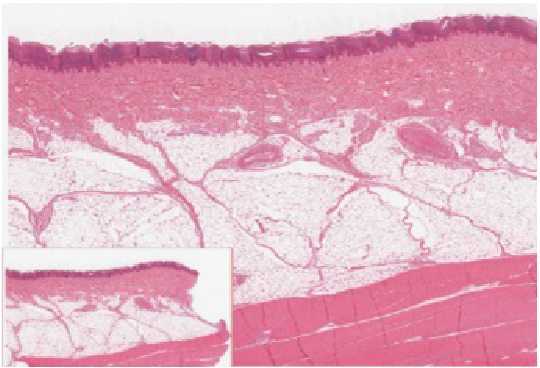

Hypodermis

The hypodermis (also called the subcutaneous layer or superficial fascia) is a layer directly below the dermis and serves to connect the skin to the underlying fascia (fibrous tissue) of the bones and muscles. It is not strictly a part of the skin, although the border between the hypodermis and dermis can be difficult to distinguish. The hypodermis consists of well-vascularized, loose, areolar connective tissue and adipose tissue, which functions as a mode of fat storage and provides insulation and cushioning for the integument.

Lipid Storage The hypodermis is home to most of the fat that concerns people when they are trying to keep their weight under control. Adipose tissue present in the hypodermis consists of fat-storing cells called adipocytes. This stored fat can serve as an energy reserve, insulate the body to prevent heat loss, and act as a cushion to protect underlying structures from trauma.